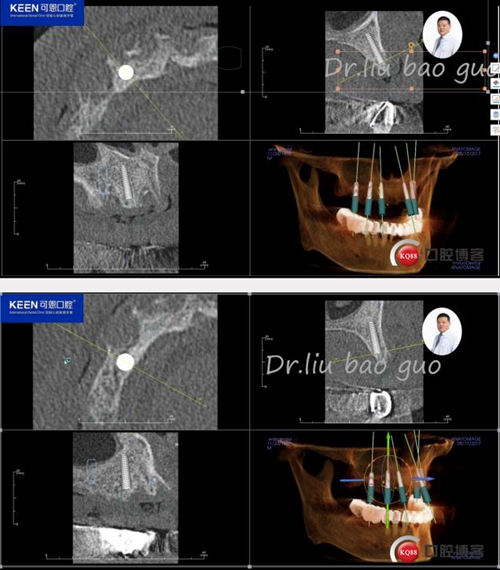

手術(shù)前種植軟件設(shè)計(jì)方案

數(shù)字化種植導(dǎo)板設(shè)計(jì)及制作

治療方案:建議上頜種植16,14,12,22,24,26,種植后即刻負(fù)重